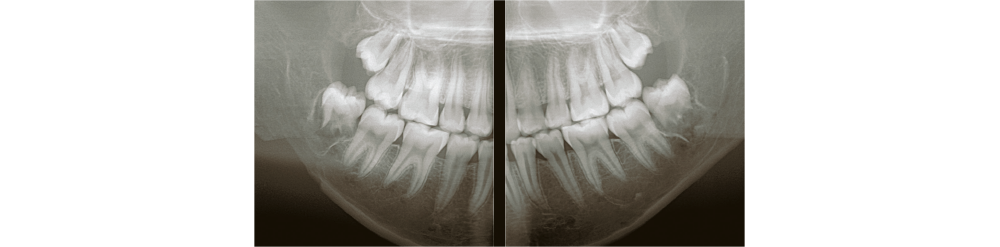

With dentists from various fields of expertise as advisors, we have carefully selected FOVs that are commonly used in clinical practice. In addition to the 3D analysis function for image detail sizes of 5x5cm, 10x10cm, 15x10cm and 15x16cm, the device features “True” and “Reconstructed” panoramic modes. With one of the largest FOVs on the market, the PreXion3D EXPLORER helps to develop the best therapy options, particularly in oral and maxillofacial surgery, airway analysis and orthodontics, as well as ear, nose and throat medicine. The use of a large 25.4x31.7cm FPD enables 15x16cm FOV scanning in one rotation.

The precise and high-resolution display of hard and soft tissue enables outstanding diagnostics and planning across all areas of modern dentistry and maxillofacial surgery. A large high-definition FPD allows all FOVs scanned in a single rotation without using stitching function.

With many 3D imaging systems on the market today, high-quality images are often accompanied by high radiation exposure. The PreXion3D EXPLORER offers balance of both aspects. The PreXion3D EXPLORER utilizes the industry’s smallest 0.3mm x-ray tube focal spot and voxel sizes from 0.07mm to 0.3mm for all FOV sizes. In addition, by adopting a high X-ray tube voltage of 110kV, pulsed X-ray irradiation, 16bit gray scale, and a newly developed large FPD, it simultaneously achieves high-definition image quality for a wide range of dental clinical practice and low radiation exposure for patient safety.